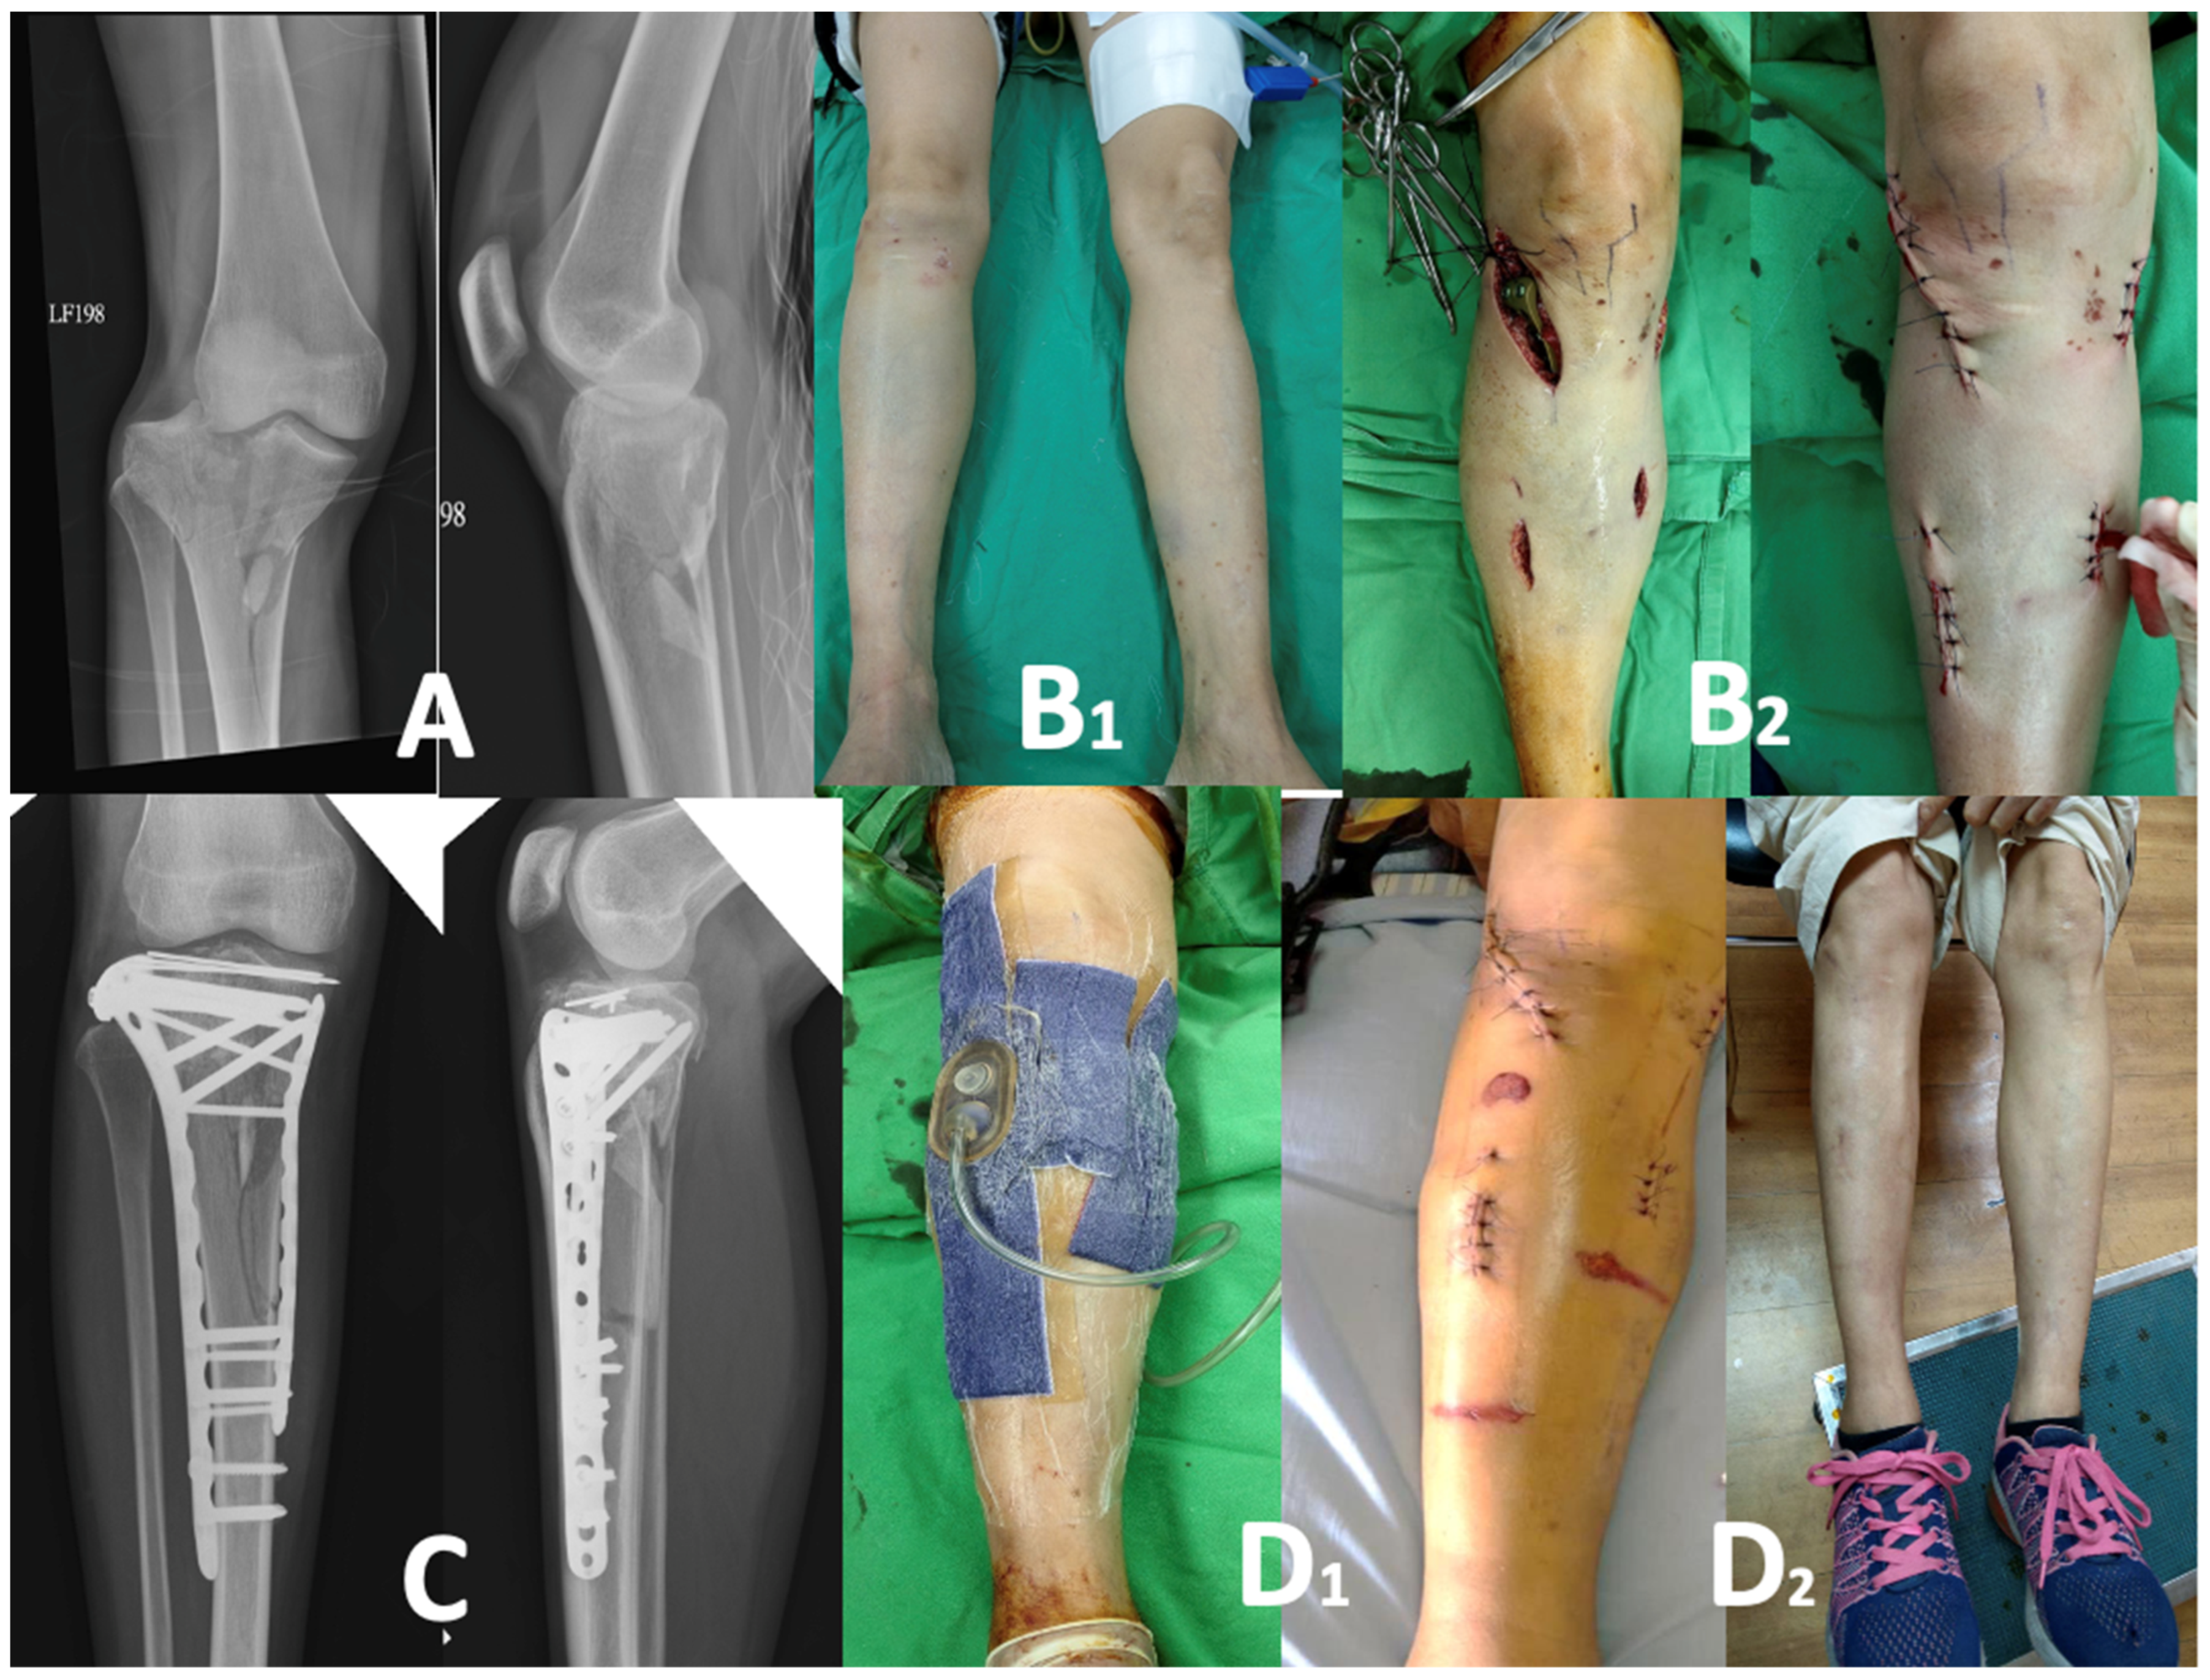

2.2. Surgical Procedures